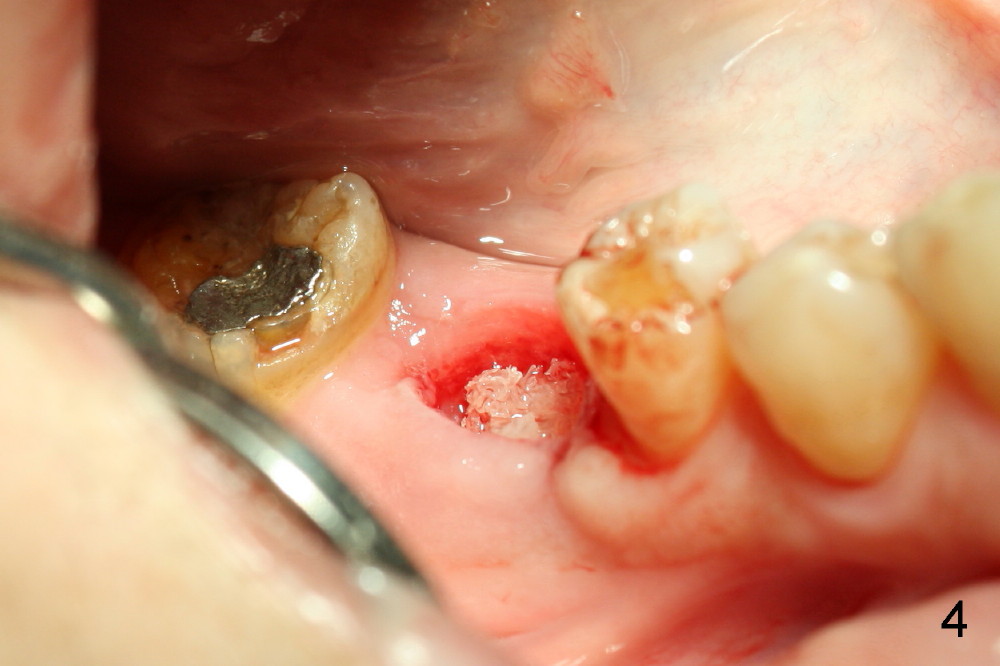

The tooth #30 was extracted in other office 1 month ago. The socket appears to heal normally. A tissue-level implant is placed as planned and smoothly. No antibiotic is prescribed pre- or post-op. The patient reports mild pain 1 week postop. There is a sign of infection. Amoxicillin is prescribed. One week later, the symptom improves, but the infection signs are present (Fig.1). The implant has mobility and is removed (Fig.2). The osteotomy is thoroughly debrided, followed by copious irrigation with normal saline and Clindamycin soaking. Irradiated cancellous bone graft (.5 mg) is placed (Fig.3,4). The wound is covered by collagen plug (Fig.5) and sutured with Chromic gut (Fig.6). Amoxicilin is prescribed postop. One week follow up reveals normal wound healing (Fig.7 (buccal view), 8 (lingual)).